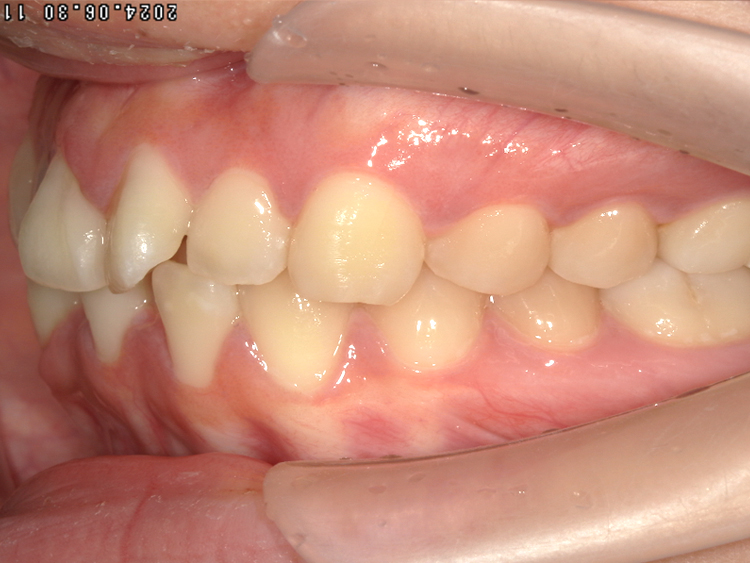

症例5

Before

After

| 主訴 | 上下3-3の並びが気になる |

|---|---|

| 年齢 | --- |

| 治療 期間 |

約1年 |

| 治療 内容 |

インビザライン5-5 |

| 治療費 | ¥517,000(税込)/調整料含む |

| 治療のリスク | 奥歯を動かさないので、前に出して並べていく。 歯と歯が移動するスペースを作るので、知覚過敏の症状がまれにでる。 歯を動かすことで、歯茎が下がるリスクある。 矯正終了後は、リテーナーを使用し、後戻りを防ぐ必要がある。 |